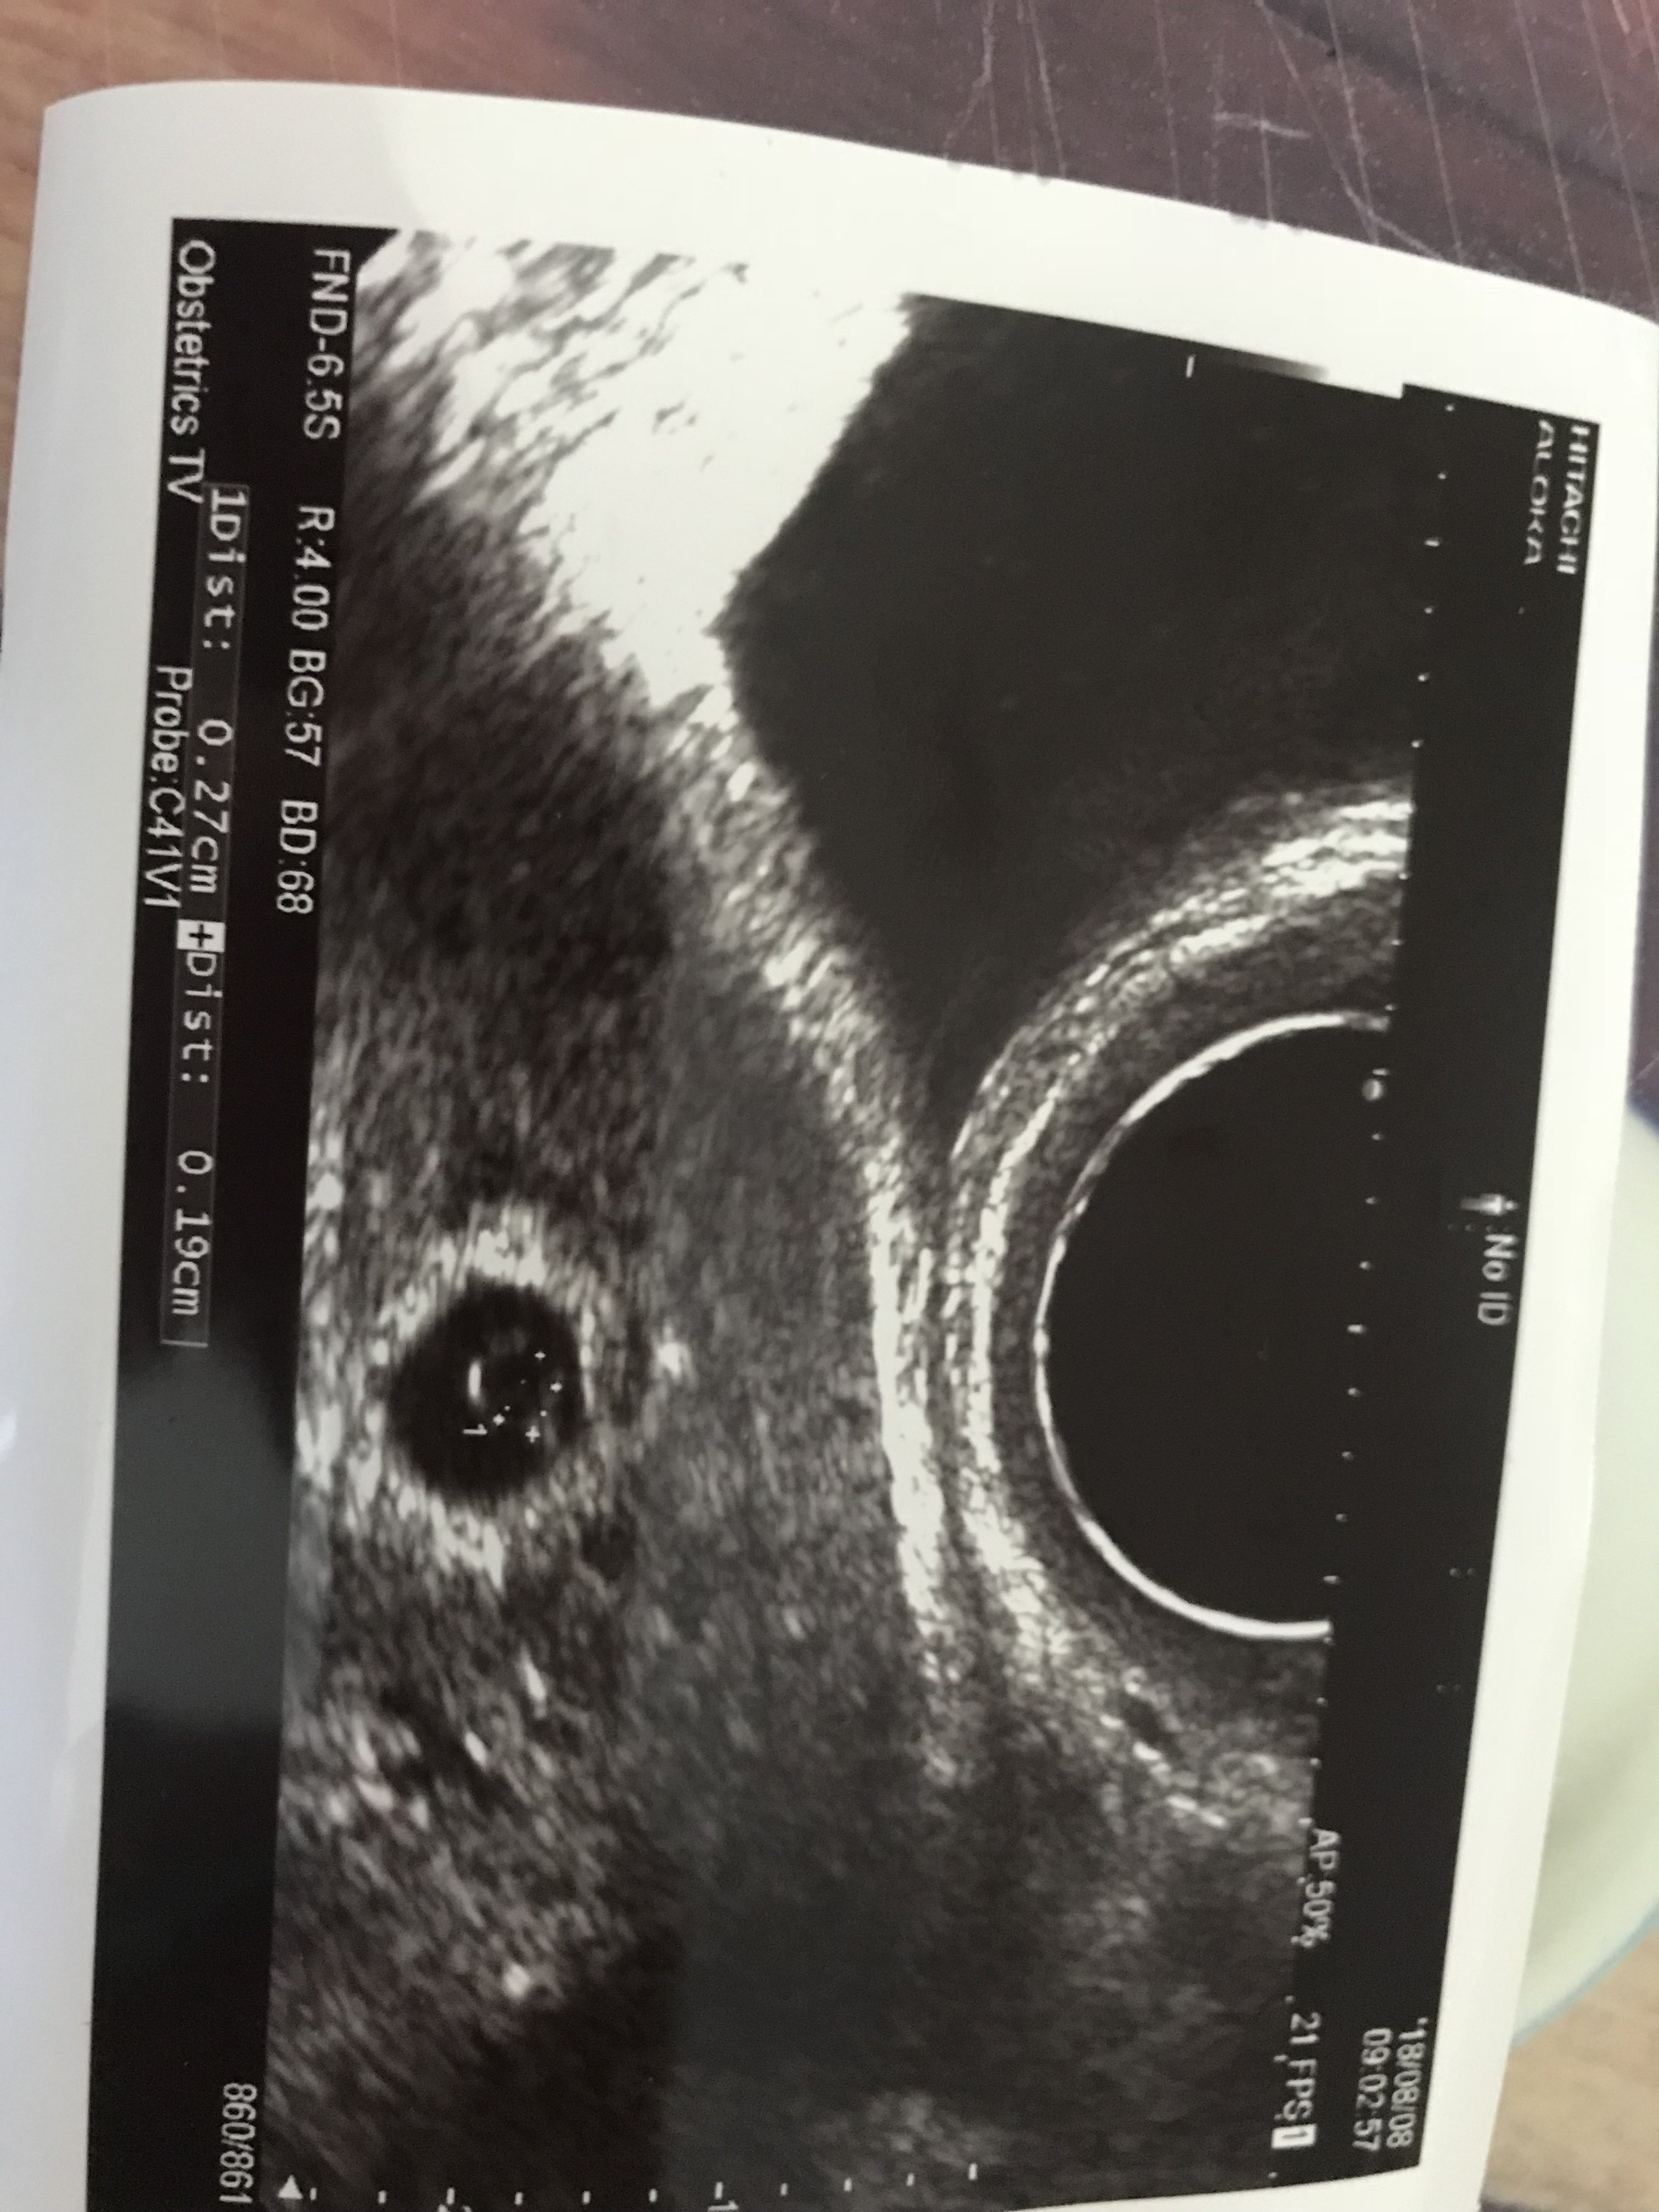

Wspaniała nowina gratulacje ❤❤❤U nas wszystko pięknie dzieciątko ma 1,9 mm serduszka jeszcze nie widać jest pecherzyk zolkowy czy jakoś tak mam przyjść w środę i już będzie serduszkocud mój trwa i jest pięknie

Jest cudownie lekarz powiedział ,ze jest wszystko dobrze zarodeczek ładnie wyglada i ciałko żółte o tak to się nazywało jestem najszczęśliwsza kobieta pod słońcem

wierzyłam w moje maleństwo i ono pokazuje ,ze jest i się dobrze rozwija teraz tylk serduszko w środę